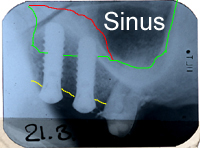

Abb. 2 - ortsständiger Knochen im Oberkiefer links vertikal 8 mm (viel!)

Abb. 3 - Sinuslift mit gleichzeitigem Setzen von drei Implantaten im Oberkiefer rechts. Transplantationsgemisch: 2/3 Eigenknochen und 1/3 Substitut.

Verlauf des Kieferhöhlenbodens vor

Sinuslift

Verlauf des Kieferkammes

-Gebiet zwischen gelber und grüner

Linie: ortsständige Knochenhöhe.

neuer Verlauf des Kieferhöhlen-

bodens nach Sinuslift.

-Gebiet zwischen roter und grüner

Linie: Knochenaufbau, Sinuslift.